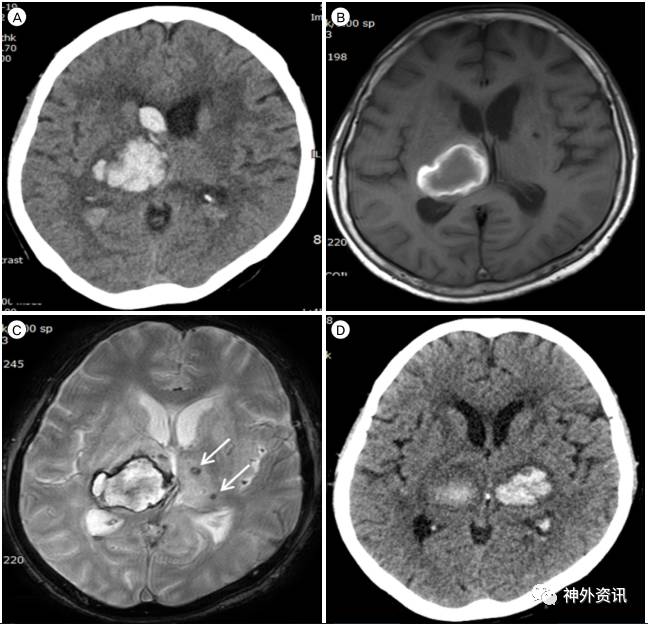

图1. A.初次发病时CT扫描示右侧丘脑出血破入脑室;B、C.起病后15天MRI显示右侧丘脑亚急性血肿伴左侧丘脑微出血灶(箭头);D.第17天CT显示左侧丘脑血肿。

65岁女性患者,因昏睡和左侧肢体肌力减退入院。长期口服5mg苯磺酸氨氯地平,血压控制良好。实验室检查未见凝血功能障碍。CT扫描显示右侧丘脑出血破入脑室。保守治疗15天后MRI检查,示右侧丘脑亚急性血肿伴对侧丘脑微出血灶;患者的意识水平和肌力逐渐好转。第17天,患者突然出现强直性阵挛发作,急诊头颅CT发现左侧丘脑血肿(图1)。椎动脉血管造影未见丘脑穿支动脉动脉瘤。随后患者处于昏迷状态,四肢肌力减退。